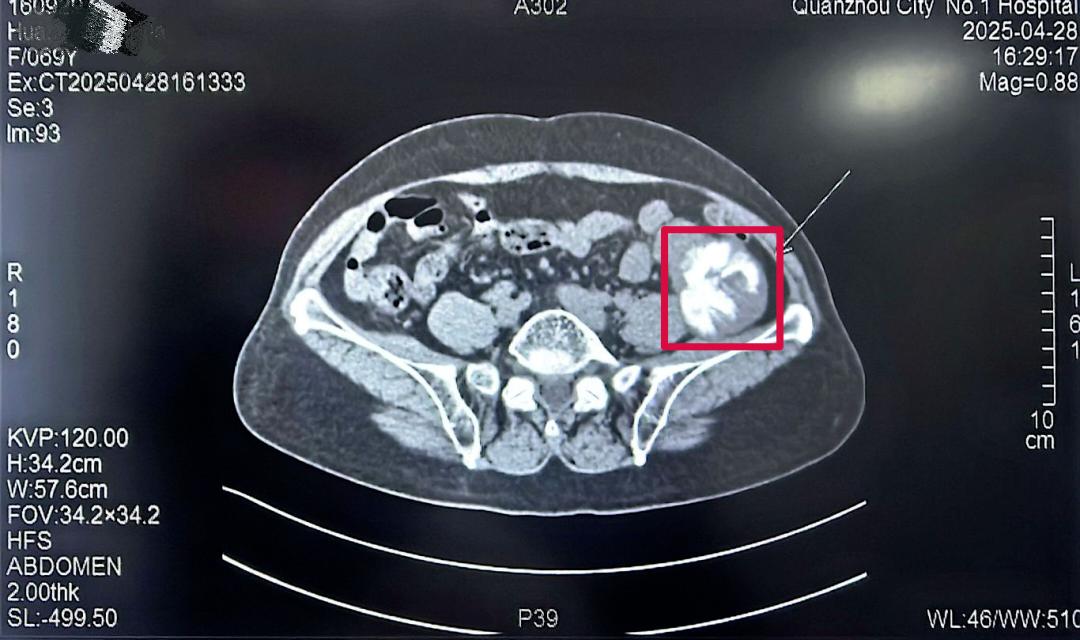

69歲的黃女士(化名)最近有些不安,她在自己左下腹部無意間摸到了一個腫塊,足有蘋果大??!焦急之下,她前往醫(yī)院進行CT檢查,但結果卻讓她的心懸了起來,在她的左下腹腔發(fā)現(xiàn)一個巨大占位,里面還有鈣化(骨頭樣結構)。面對這個陌生的診斷,黃女士和家人一時手足無措,對治療方案充滿疑慮。

幾經(jīng)了解問詢,黃女士找到了泉州一院胃腸外科的林鴻悅主任團隊。林主任仔細詢問了病史,為她做了詳細檢查,并認真研判了CT影像,初步判斷,這極可能是一個長在腹腔深處(腹膜后)的腫瘤,位置刁鉆,且情況復雜。

林鴻悅主任團隊迅速組織了術前討論。深入分析病情后,團隊意識到這次手術極具挑戰(zhàn)性,這個腫瘤長在“腹膜后”。這個位置就像腹腔的“后倉庫”,空間狹窄,里面“住”著人體最重要的大血管(如腹主動脈、下腔靜脈)、神經(jīng)叢和器官(如腎臟、胰腺、腸道)。手術稍有不慎,就可能引發(fā)難以控制的大出血或損傷關鍵臟器,后果不堪設想。

同時這個腫瘤性質罕見且兇險,初步影像提示腫瘤伴有鈣化(骨頭樣結構),團隊高度懷疑這是一種極其罕見的惡性腫瘤--去分化脂肪肉瘤伴骨肉瘤分化。這種腫瘤不僅惡性程度高、侵襲性強,而且其中的“骨肉瘤分化”成分,意味著腫瘤內部可能像骨頭一樣堅硬,大大增加了完整剝離的難度。